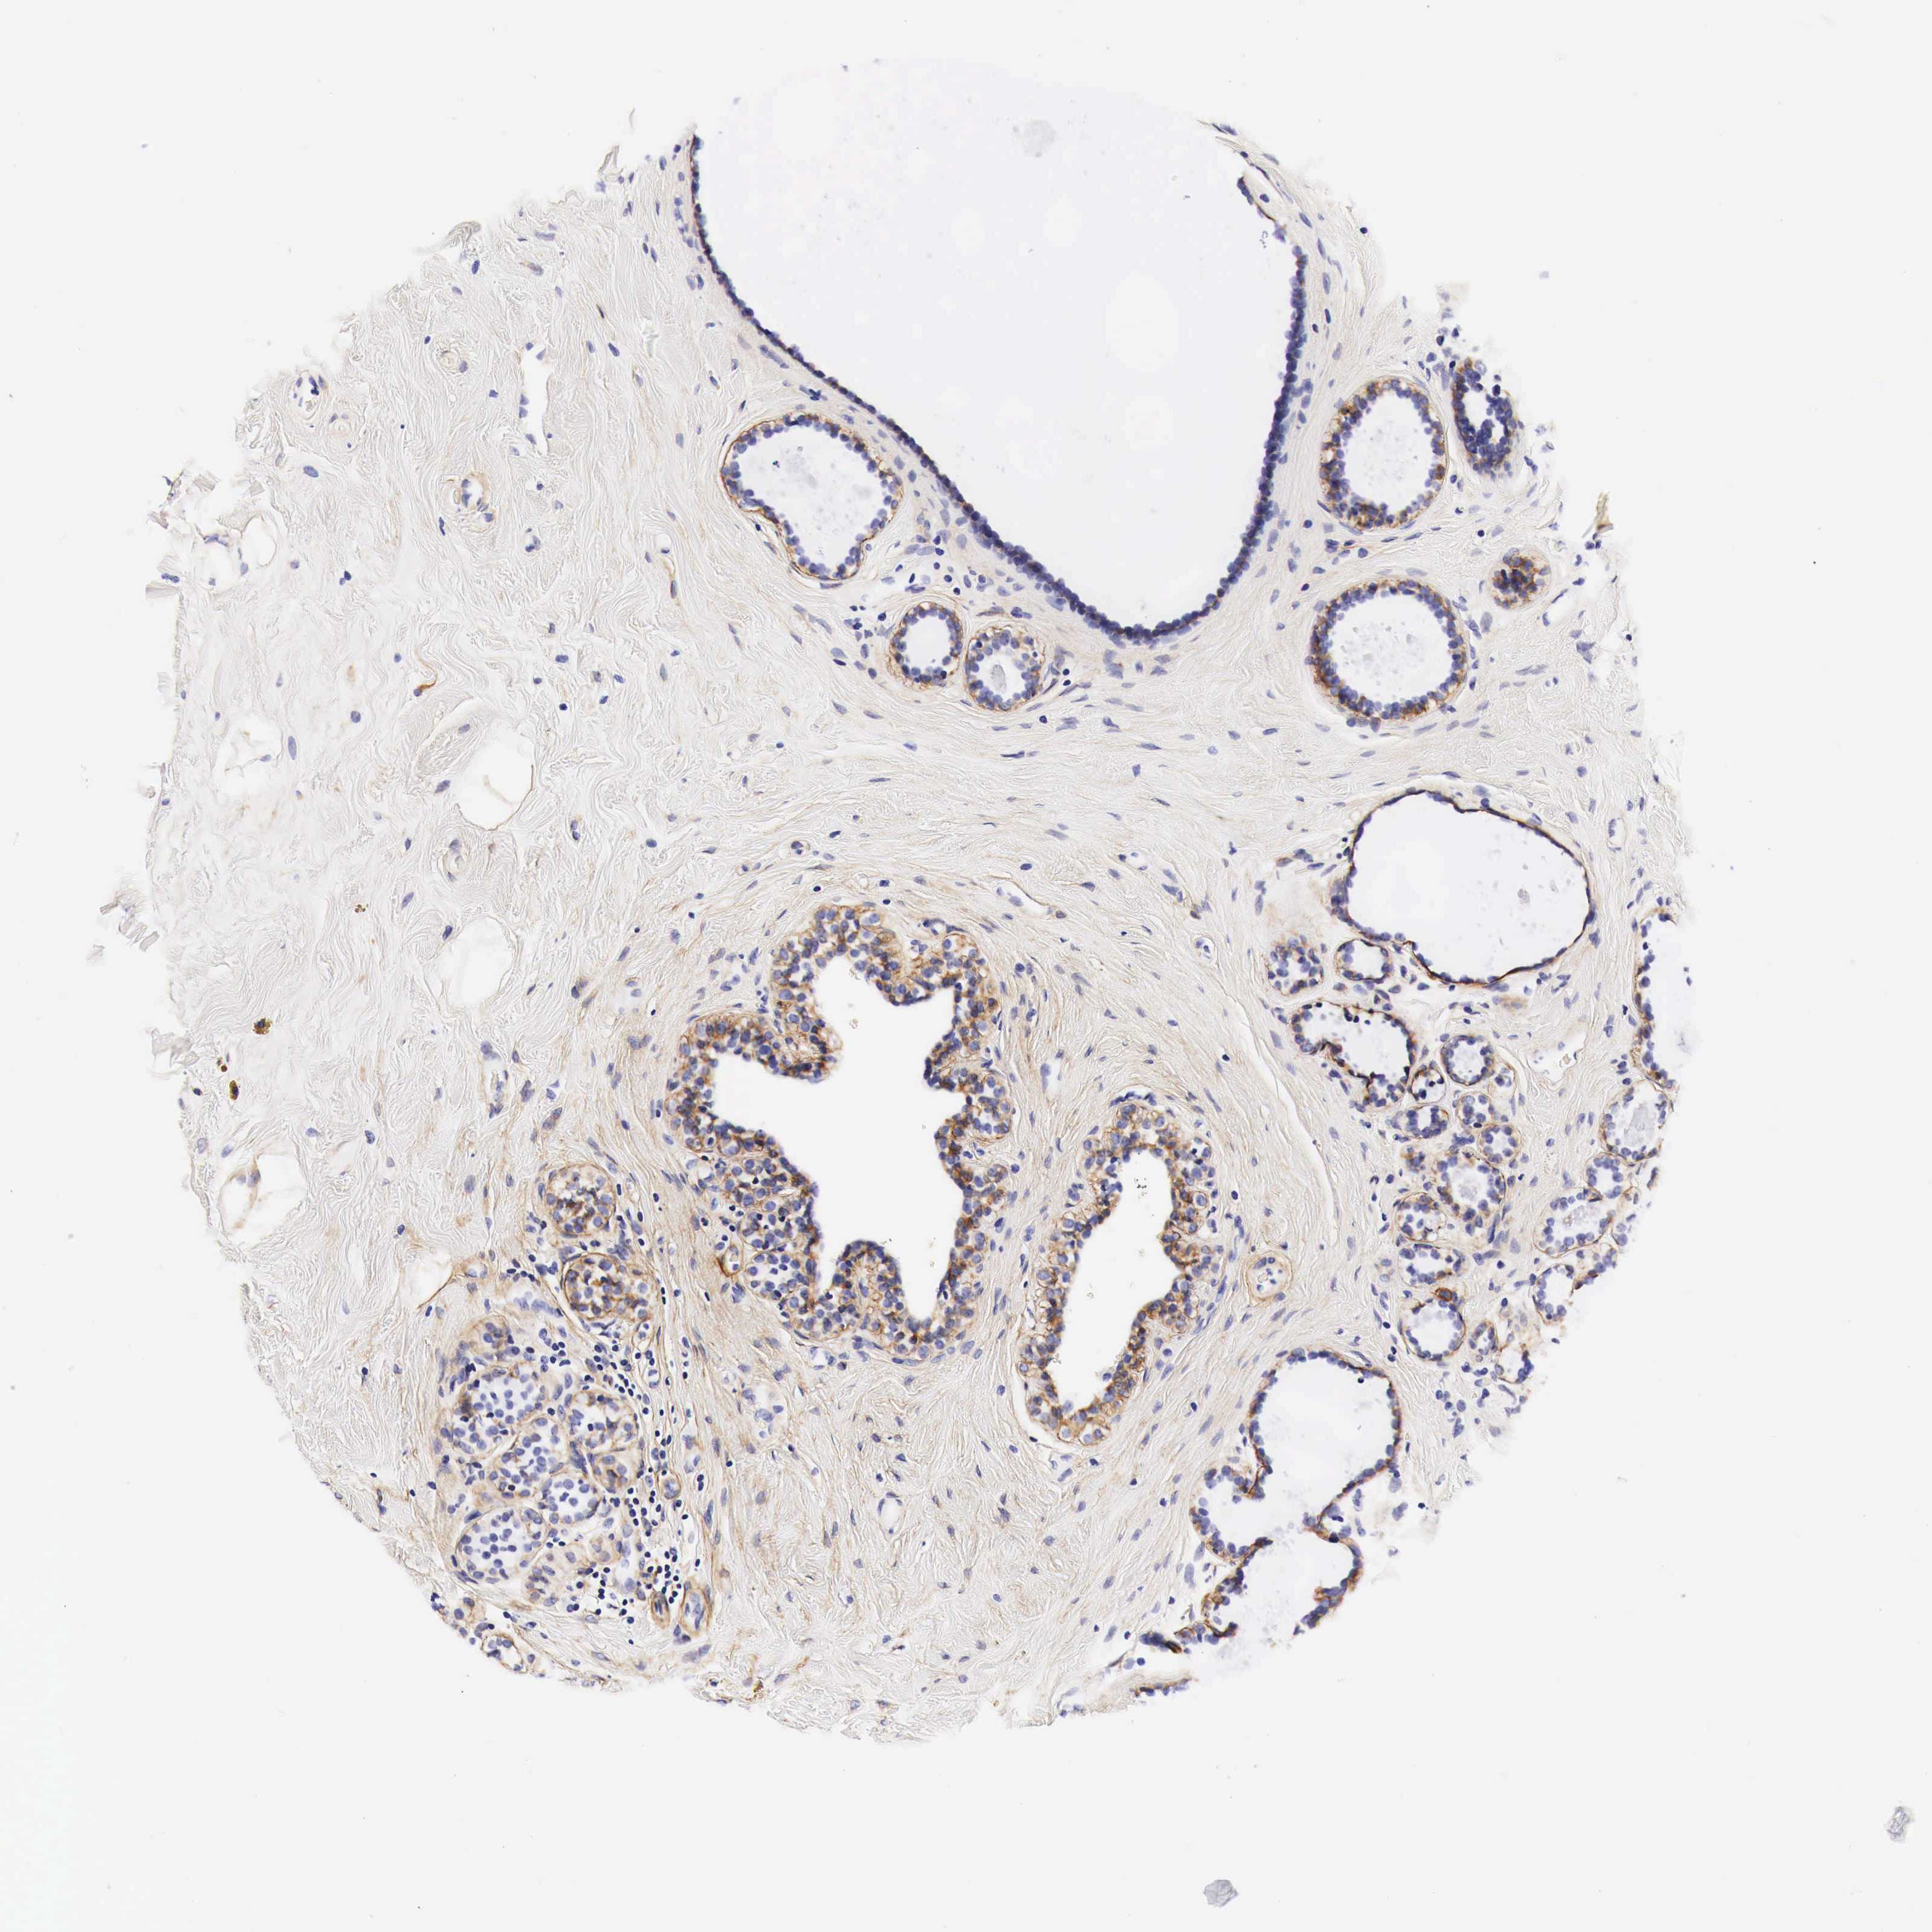

BRCA TCGA BRCA VALIDATION PROTEIN EXPRESSION